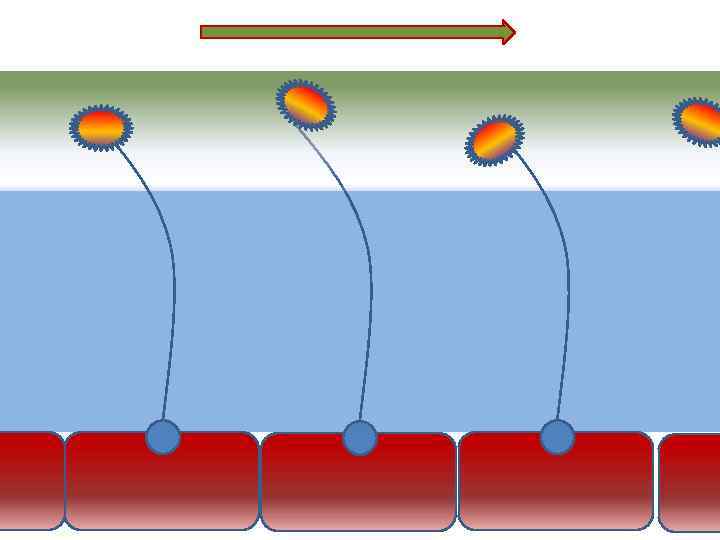

Движение клеток реснитчатого эпителия Движение вперед 1 – 3 Обратное движение 4 – 8

Движение клеток реснитчатого эпителия Движение вперед 1 – 3 Обратное движение 4 – 8

Оптимальное увлажнение Достаточная продукция слизи Хороший транспорт Экономит энергию и воду Защитная функция

Оптимальное увлажнение Достаточная продукция слизи Хороший транспорт Экономит энергию и воду Защитная функция

Механизм защиты легкого Слизь (зеленый цвет) нейтрализует и связывает патогенную флору(синий цвет) Слизь – это барьер между клетками и патогенной флорой Слизь – это транспортное средство

Механизм защиты легкого Слизь (зеленый цвет) нейтрализует и связывает патогенную флору(синий цвет) Слизь – это барьер между клетками и патогенной флорой Слизь – это транспортное средство

Нормальное состояние слизистого бронхиального секрета возможно только при 100% относительной влажности воздуха

Нормальное состояние слизистого бронхиального секрета возможно только при 100% относительной влажности воздуха